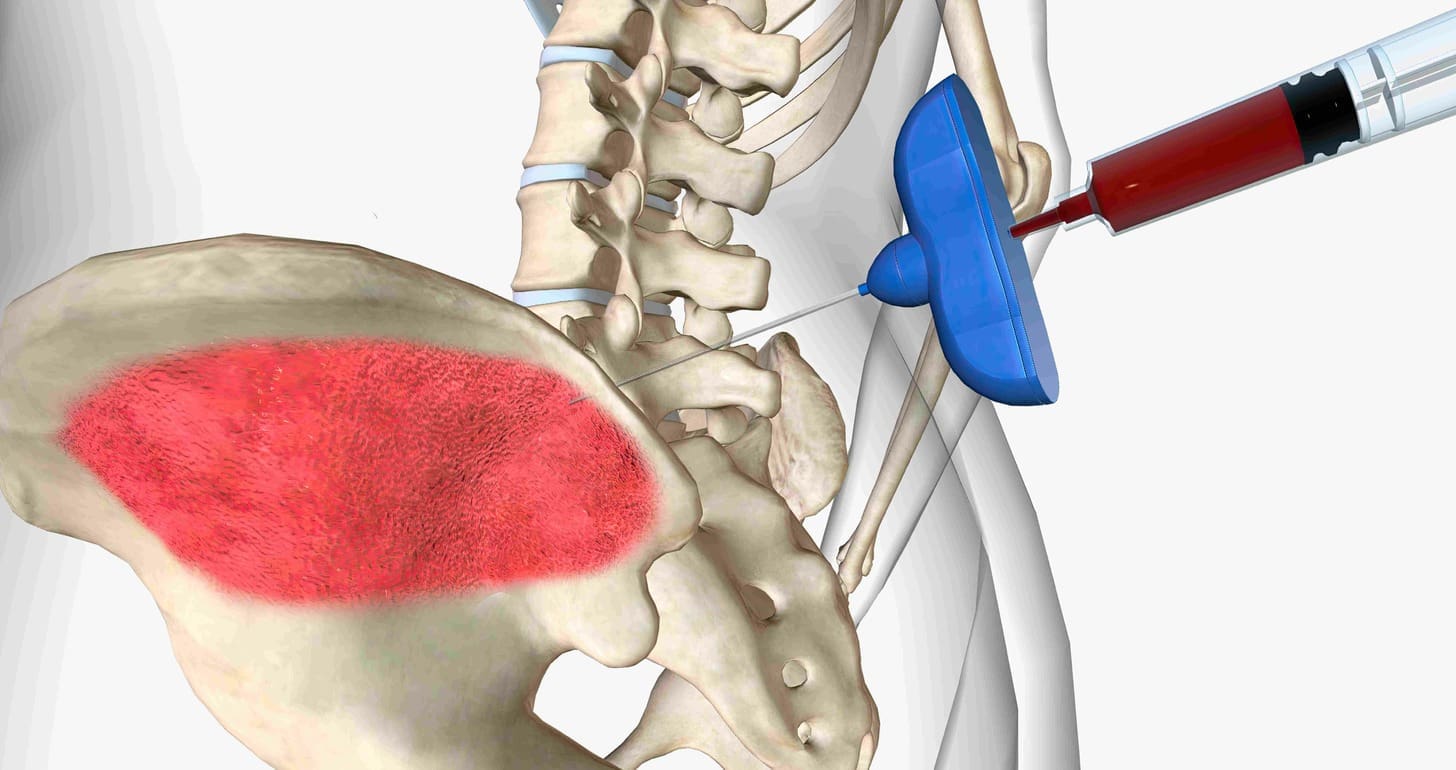

Pacemaker Indications

Getting a permanent pacemaker is a common solution for third-degree AV block. It’s often recommended for those with symptoms, as it can greatly improve their life and chances of living longer.

Pacemakers help the heart beat at the right speed and rhythm. Doctors decide if a pacemaker is needed based on symptoms, the cause of the block, and the patient’s health.